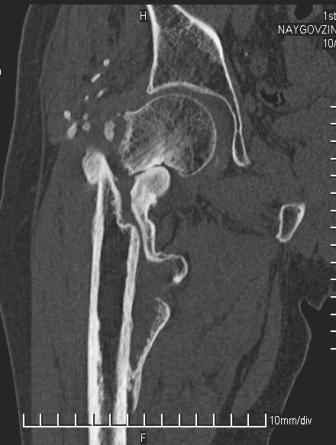

Больной Н. 44 года травма 1,5 года назад июнь 2008 года чрез-под вертельный перелом правого бедра. Во время лечения у больного развился алк. делирий, проводилось консервативное лечение перелома.

Беспокоят боли, укорочение конечности.Укорочение 3 см. Ногу поднимает, сгибание ограничено, ротационные движения в полном объеме.На КТ перелом сросся за счет костной мозоли.Что делать?

Уважаемый Глеб, боли из-за ложного сустава шейки бедра. Сращения там нет.

Тазобедренный сустав сохранный и возраст пациента позволяет побороться. Согласен с Максимом, попробуйте остеотостеотомию.

Уважаемый Глеб! Укорочение наверное побольше, да и наружно-ротационная установка скорее всего присутствует. Суставная щель прекрасная, головка живее всех живых. Ратую за подвертельную с латерализацией: исключает нарушение механической оси («исключает вальгус в коленe»), максимально удлиняет без натяжения m.iliacus. Для иллюстрации остеотомия-переделка (слава богу не автопеределка) у мужчины 65 лет.